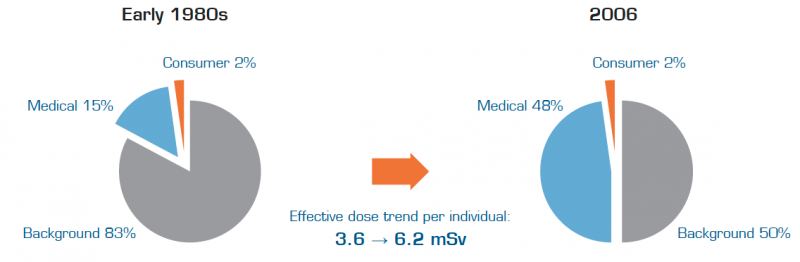

The significant increase in radiation exposure and uncertainty regarding the risk of cancer have raised concerns leading to a recent change of direction within medical imaging. Several initiatives to lower dose levels are being established and many healthcare providers have initiated dose reduction programs to guard patient safety and to comply with new regulations.

The radical increase in patient exposure to radiation from medical imaging over the last two decades has created great concerns about its inherent risks. Today, one of the highest priorities on many hospital agendas is to break this trend by achieving improved control of the radiation exposure to their patients.